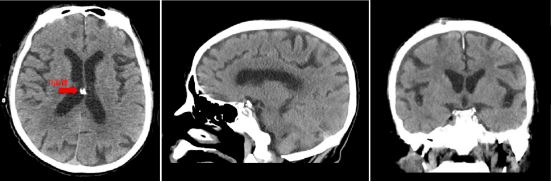

高龄、卧床患者的护理一直是临床工作中最有挑战性的环节之一,赵雪莲护士长精心安排病房护理骨干轮流值班,严密看护刘爷爷的病情变化,照顾患者的饮食起居。脑室外引流过度的话,会导致颅压过低、硬膜下积液及出血等并发症,如果引流过少的话又起不到作用。为了达到最好的治疗效果,每班的主管护士每隔1-2个小时就要查看刘爷爷的引流情况,严密观察引流的形状、总量等,按需及时调整引流管高度。经过医护人员2周的精心护理和治疗,刘爷爷脑室内的出血全部排除干净,顺利康复出院。

图3 头颅CT提示脑室内出血全部排出